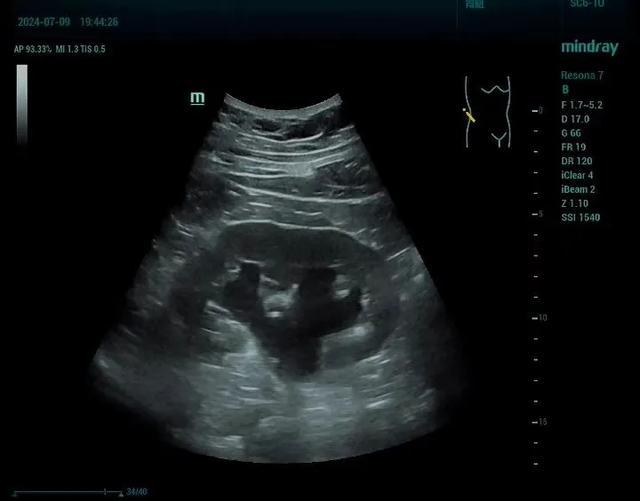

五、首选检查方式

泌尿系超声:无创、快捷,既能显示结石,又能定位梗阻部位,还能判断积水程度及肾脏实质改变。